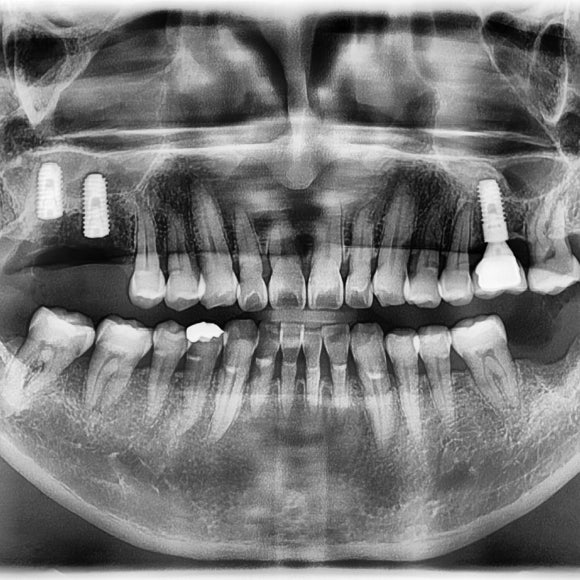

발치를 하고, 상악동 거상술과 뼈이식을 진행 하였음.

뼈가 단단해 질 때 까지 6개월 이상 충분한 치유기간을 준 후

보철물 머리를 올리게 될것.

병을 방치하고 많이 진행된 상태에서 치료가 들어가면

치료 예후와 치료 기간 그리고 비용이 갑절이 될 수 있으므로,

치료를 해야할 곳이 있다면 미리미리 하는게 중요함.